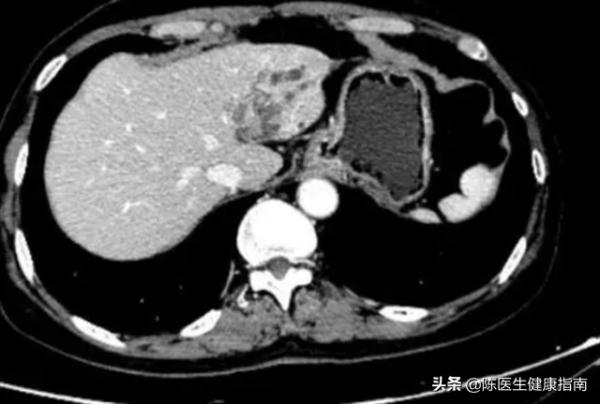

患者體溫36.8℃、血壓124/85、身高179cm、體重73kg。患者身體發黃,腹部存在大量腹水,輕觸有疼痛感。肝功能嚴重受損,腹部超聲提示:肝囊腫,肝臟瀰漫性腫大,考慮為肝硬化。